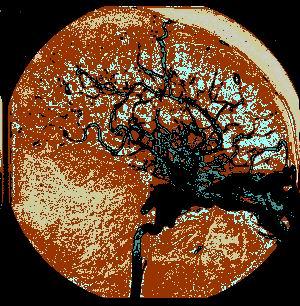

问题 病历摘要:??患者女性,25岁。10日前因车祸致头部外伤,伤后有短暂昏迷史,右鼻腔少量血性液体流出。8日前开始感颅内有杂音。7日前右眼睑出现肿胀伴右眼视力下降,并逐渐加重。既往体健。体检:神志清楚,右眼明显突出并有搏动,右眼睑及球结膜水肿充血,眼球部及颞部可听到与脉搏一致的隆隆样杂音。瞳孔右大于左(5:3mm),视力右眼失明,右眼球各方向运动均受限,左眼视力及运动正常。 下列关于颈动脉海绵窦瘘的叙述哪些是正确的?

选项 A.按病因可分为:外伤性颈动脉海绵窦瘘、自发性颈动脉海绵窦瘘 B.按部位可分为:颈内动脉海绵窦瘘、颈外动脉海绵窦瘘 C.按瘘口可分为:单纯性颈动脉海绵窦瘘、复杂性颈动脉海绵窦瘘 D.最明显的表现是搏动性突眼和颅内血管杂音 E.因外伤引起者多见 F.目前最主要的治疗方法是血管内栓塞 G.血管内栓塞术中,最常用的方法是经动脉途径球囊栓塞治疗